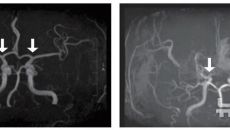

소아 모야모야병, 유병률 늘고…치명적 합병증은 40%↓

[서울=뉴시스] 류난영 기자 = 희귀난치성 뇌혈관질환 '소아 모야모야병'의 발생 양상과 치료 및 예후를 전국 단위로 분석한 결- 2025-12-05 10:02